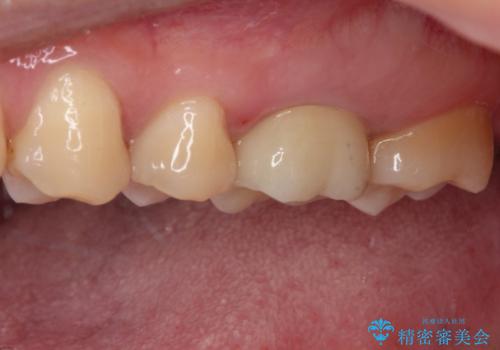

目立つ銀歯を白くしたい セラミック治療

- 矯正治療後に目立つ銀歯を白くしたいとのことで来院された患者様です。

右下の銀の詰め物は、外してむし歯を除去した後、セラミックインレーにて修復することとしました。

左上の銀歯は、銀歯の下に金属の土台が入っているため、その土台を除去し、ファイバーコアにやり替えて、オールセラミッククラウンにて補綴することとしました。

適合の良いセラミック治療は、むし歯再発のリスクが低いです。

目立つ銀歯がなくなり、患者様は大変満足されました。